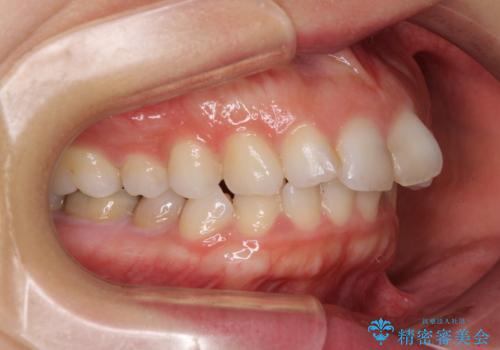

- 口元の閉じにくさと、奥歯の咬み合わせを気にして来院された患者様です。

左下の大臼歯2本が顕著に舌側に傾斜しているため、まずは奥歯の咬み合わせを改善をし、その後上下左右の第1小臼歯4本を抜歯することで口元を引っ込めながら整えることとしました。

奥歯の咬み合わせ改善には1年ほどの期間と処置中の噛みにくさを強いることとなりましたが、抜歯後はスムーズに治療を完了させることができました。

歯ぎしりの際に奥歯が干渉していた咬み合わせも理想的な状態に改善できました。